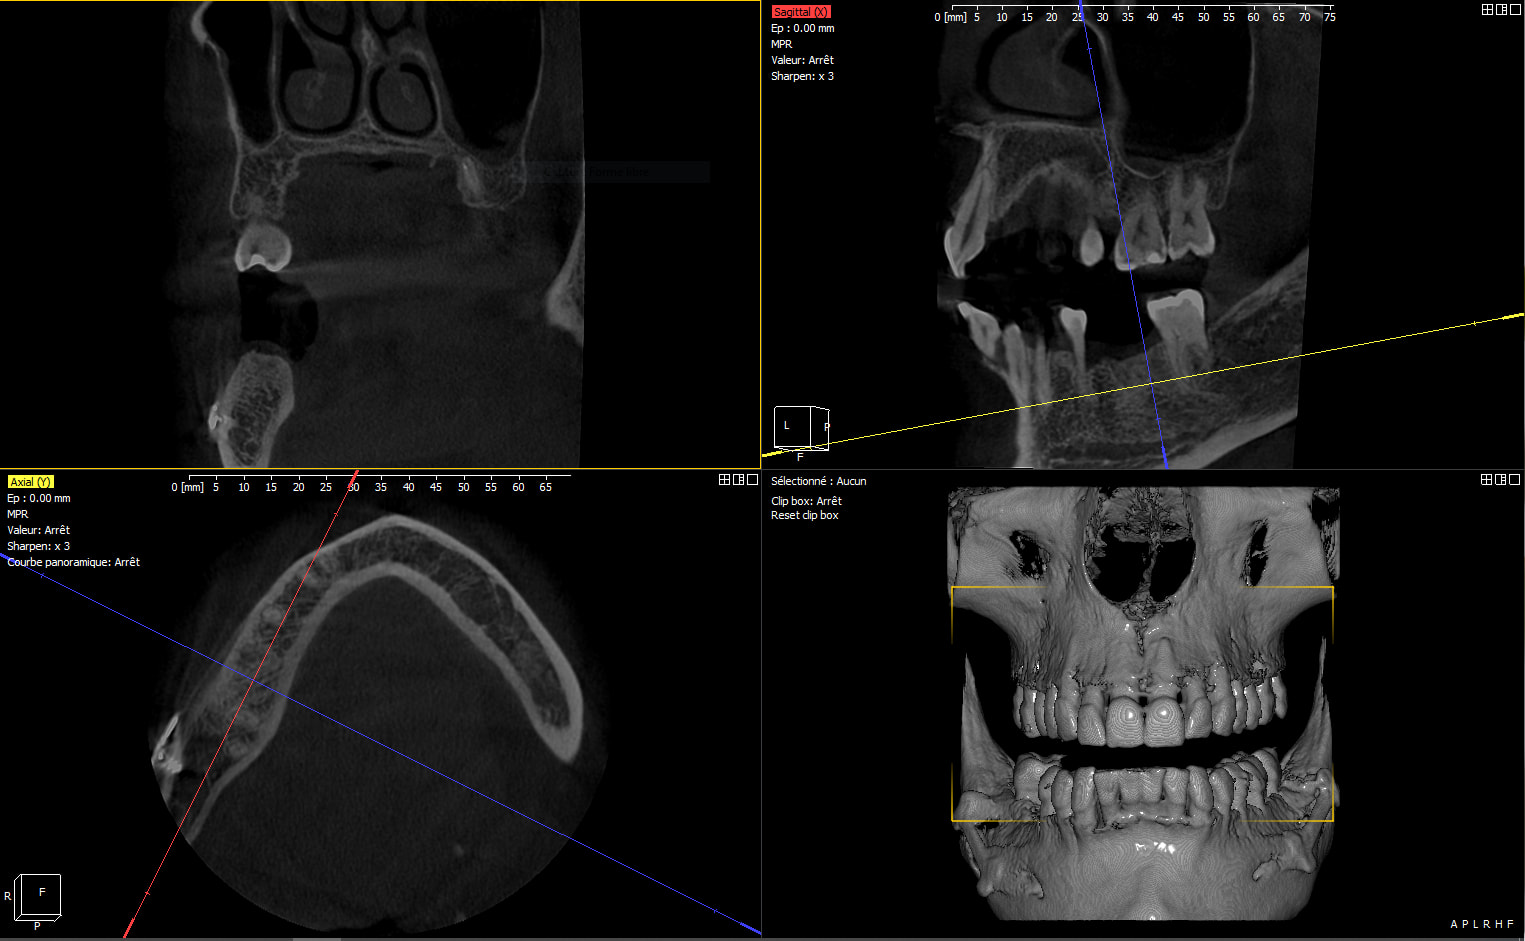

Le verdict ce matin au CBCT... Trop vestibulé (classique) même si mon axe d'émergence sort bien au niveau de la cuspide palatine maxillaire, sous forage et nécrose par compression en essayant de le tanker à la main. Dans du D1 vous avez une alternative cylindrique dans vos tiroirs ou vous restez sur du cylindro-conique ? Dépose programmée. Pour la pulpectomie de 47, je vais attendre un peu. 8 semaines vous semble raisonnable pour réimplanter ? Quels sont vos conseils pour la réintervention ? Merci à tous

Capture zsgxep - Eugenol

clairement ton image de CBCT me fait plutôt penser à un pb d'échauffement

peut être en plus augmenté par la compression générée par le design de ton implant, très classique avec le CC parce que c'est pas un implant auto taraudant, il est fait pour être compressif...

En revanche, c’est l’énorme image apicale à l’implant qui m’étonne. Tu as le CBCT, préopératoire ?